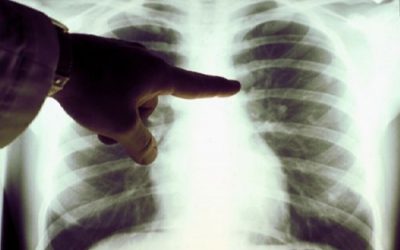

Чтобы понять, зачем нужна флюорография, следует проанализировать информацию о данной процедуре. Самым простым ответом на вопрос, что такое флюорография, можно считать объяснение этого термина как диагностического метода. Чаще всего он используется для выявления заболеваний органов дыхания и сердечных патологий. С его помощью удается обнаружить такие болезни, как туберкулез, рак, бронхит и пр.

Флюорография – это фотография изображения грудной клетки обследуемого, что получается на экране благодаря рентгеновскому излучению.

Это изображение получается очень маленьким, но этого достаточно, чтобы обнаружить отклонения в исследуемом органе. На современном этапе все чаще используется цифровая флюорография, где вместо пленки применяется цифровой носитель. Это позволяет снизить лучевую нагрузку на пациента. Но в целом метод остается таким же, как раньше.

Флюорография предполагает определенные результаты, норма для которых, это – четкий рисунок дыхательных органов. В пределах одной и той же ткани не должно наблюдаться затемнений или светлых пятен. Именно такая расшифровка флюорографии считается нормальной.

При наличии очаговых теней следует учитывать их расположение. Если они обнаружены в нижней или средней части легкого, то это признак пневмонии. Верхнее расположение таких теней позволяет предположить развитие туберкулеза.

Кроме этих, на снимке могут быть обнаружены и другие отклонения. Важно, чтобы заключение флюорографии делал врач, поскольку только он может правильно оценить выявленные особенности. Также следует учесть, что показанный на снимке результат иногда бывает ошибочным, если была нарушена техника выполнения.